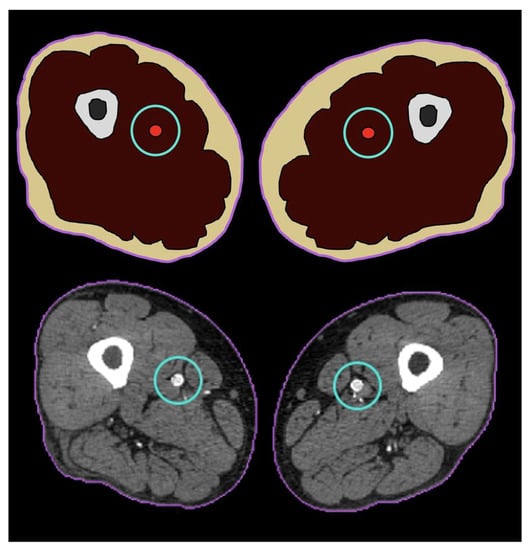

2. Materials and Methods